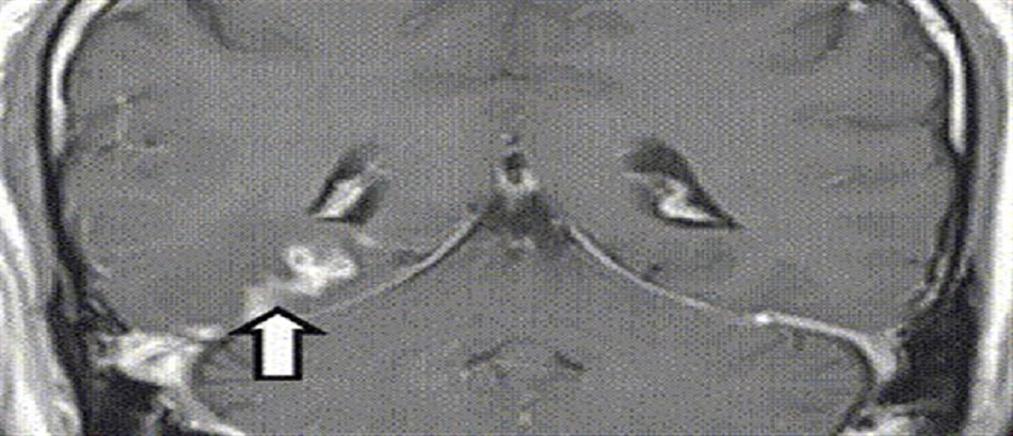

Ζωντανό σκουλήκι 8 εκατοστών βρέθηκε σε εγκέφαλο γυναίκας (εικόνες)

Αντιμέτωποι με ένα πρωτοφανές θέαμα στα παγκόσμια ιατρικά χρονικά βρέθηκαν χειρουργοί στην Αυστραλία κατά τη διάρκεια επέμβασης εγκεφάλου. Το χρονικό της υπόθεσης.